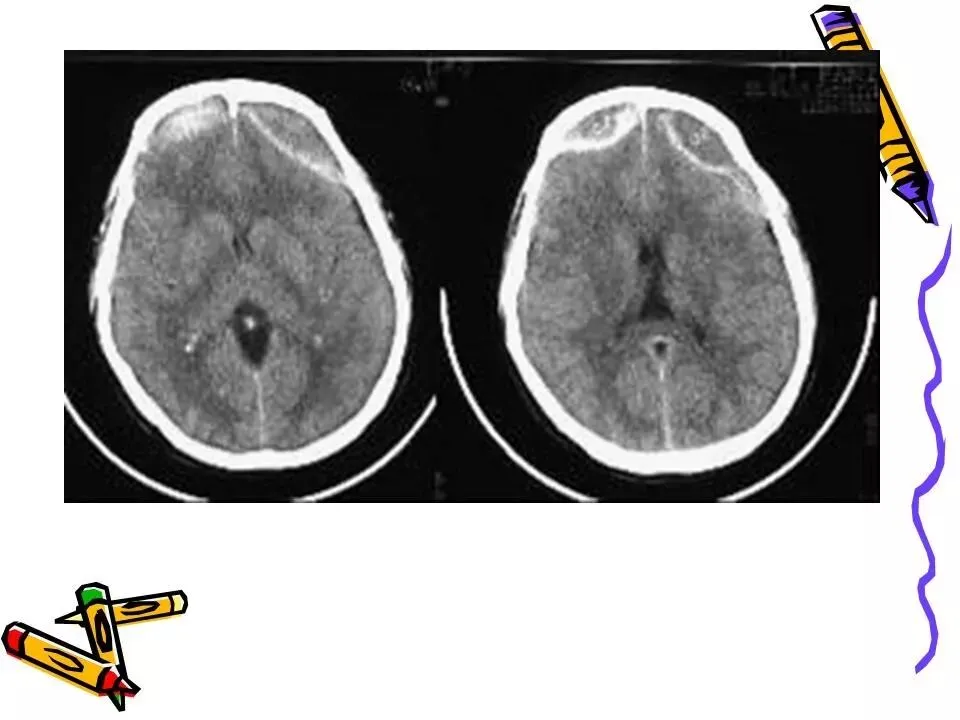

>常见颅脑外伤CT诊断(PPT)

常见颅脑外伤CT诊断(PPT)